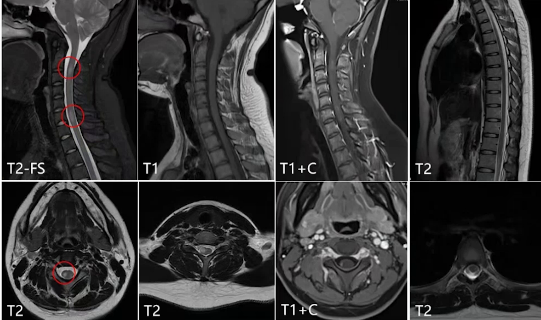

颈椎MRI平扫及增强、胸椎MRI平扫结果显示,颈椎矢状位T2WI压脂像上髓内有多处T2稍高信号的短节段病灶,轴位显示病灶位于右侧侧索,T1WI稍低信号,增强可见轻度环状强化;胸髓可见点状T2稍高信号。

(二)髓内病灶分析

对髓内病变的三种疾病进行鉴别:

·病灶数量:三者均多发,难以区分。

·病灶范围及位置:NMOSD病灶累及中央灰质及部分白质,横截面积大于2/3脊髓横断面;MS位于侧索,局灶性,边界清楚,多发短节段,每个病灶小于2个椎体节段;ADEM累及脊髓中央,为长节段病灶。

·信号特点:均为T2高信号,急性期均有强化。

结合颅内及髓内病灶分析,该病例从影像学上初步倾向于MS。

综合影像分析及临床特点补充,影像学诊断为多发性硬化。回顾病灶特点,颅内病灶多发,经典部位在脑室周围,也可位于皮质及近皮质区域,脑室周围可表现为直角脱髓鞘病灶、Dawson手指征及卵圆形,T2和T2 FLAIR高信号,增强扫描可强化;髓内病灶位于侧索,局灶性、短节段,T2高信号,急性期有强化。临床特殊检查结果显示血的AQP4阴性,脑脊液的寡克隆区带阳性,最终临床结合病史及检查,诊断为复发缓解型多发性硬化。